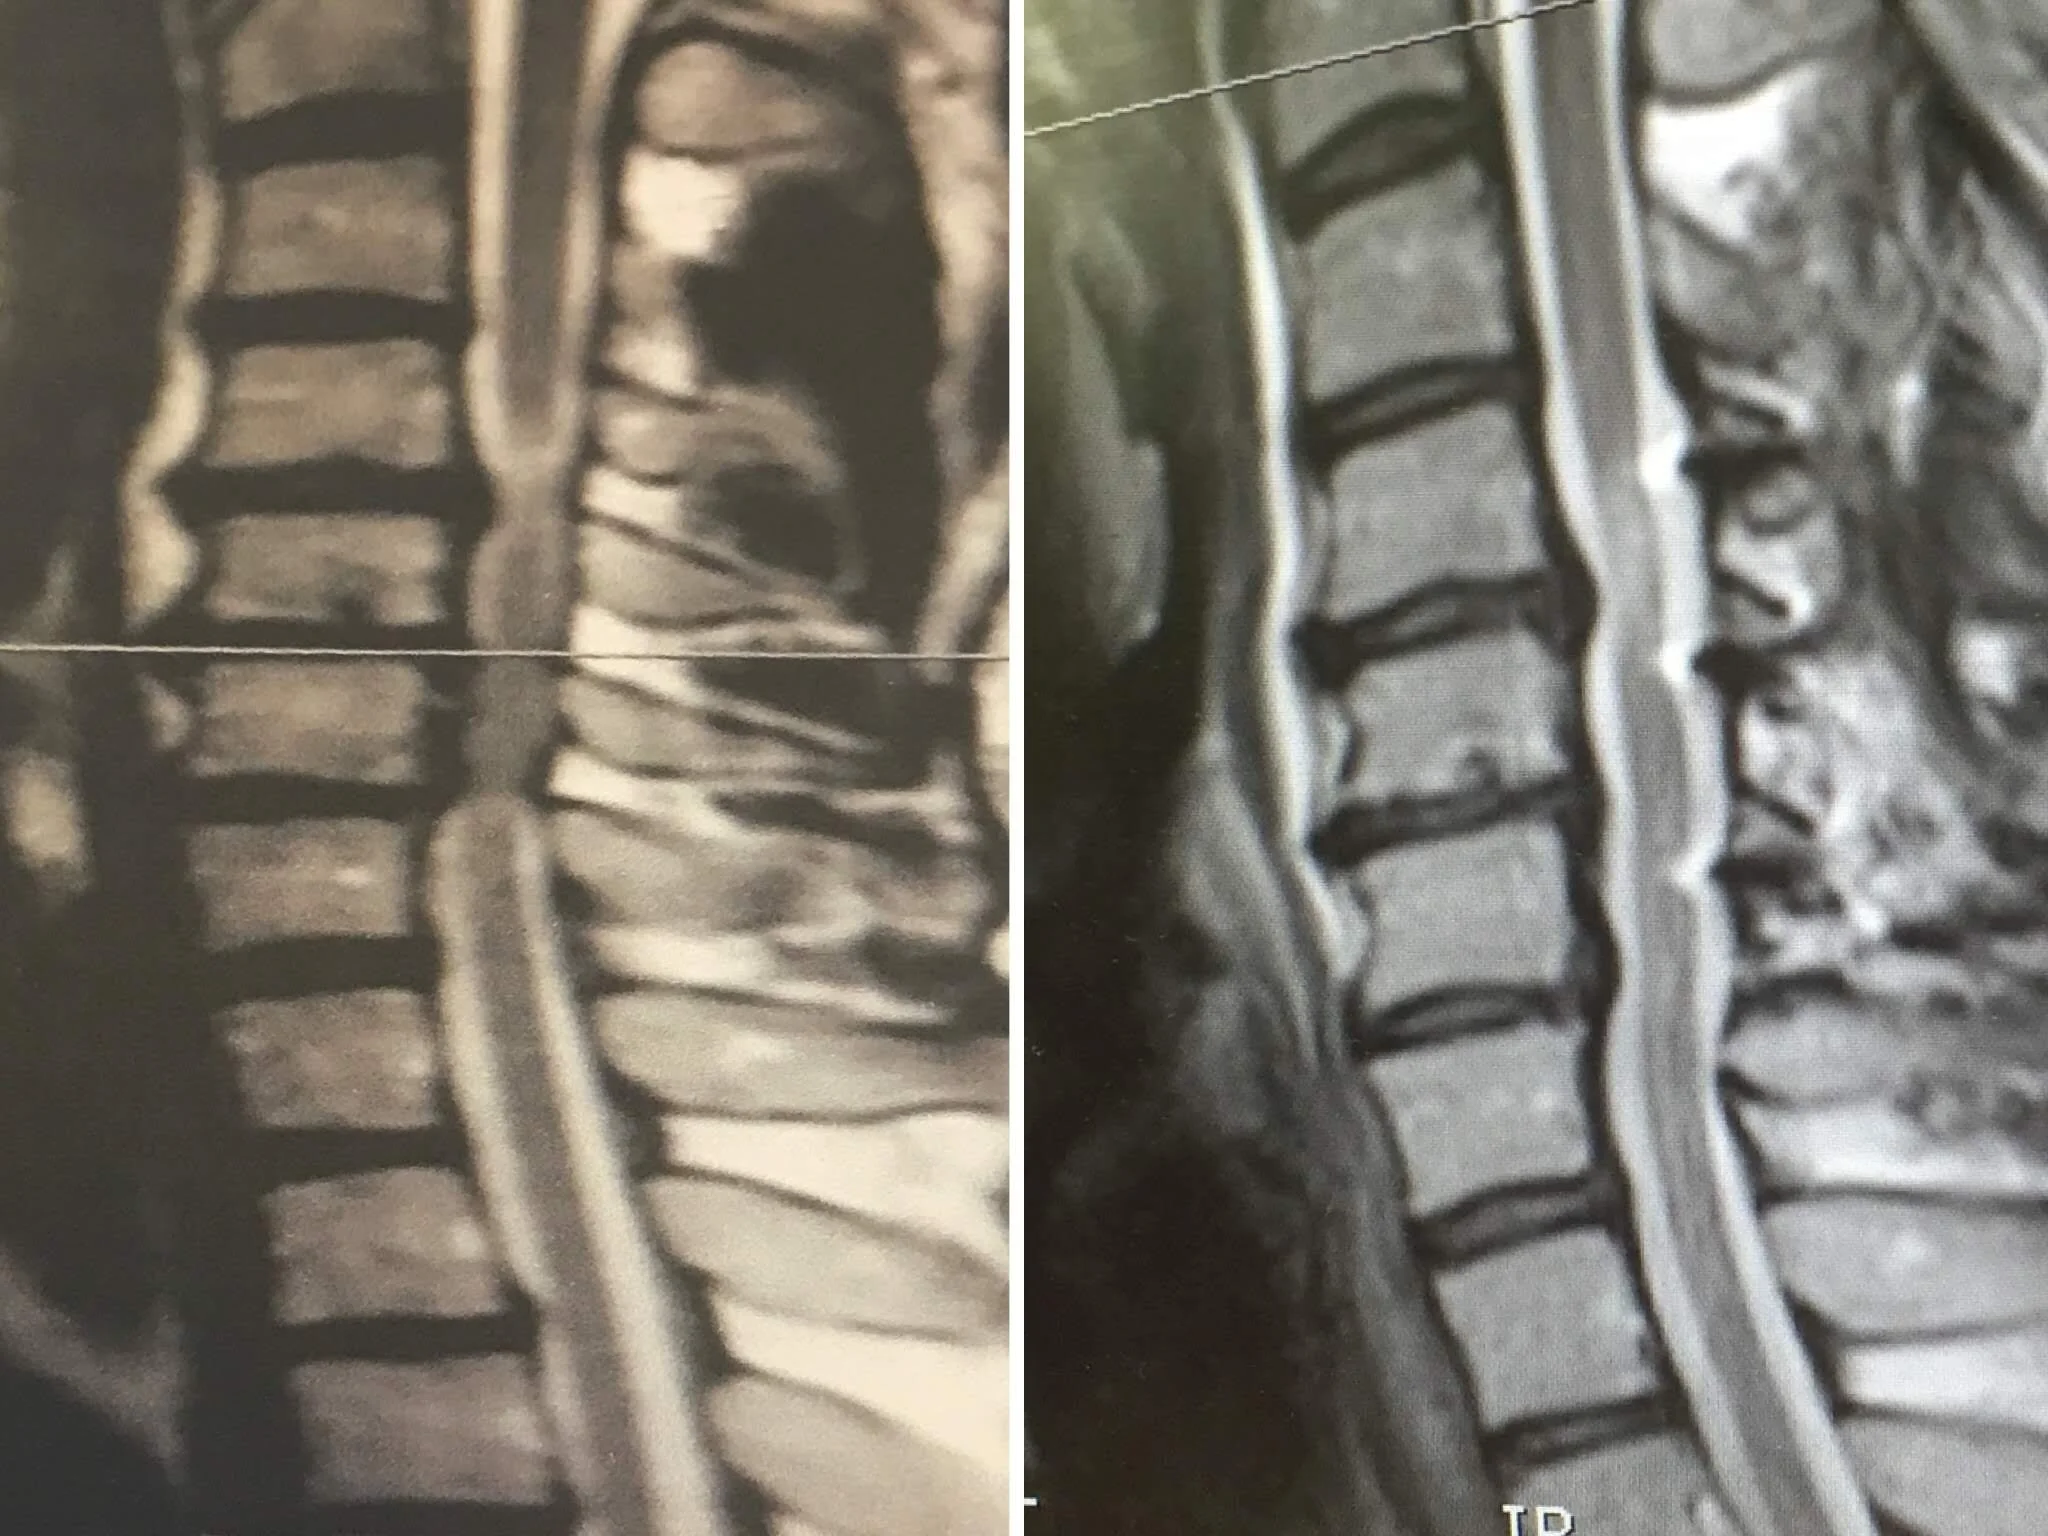

Below, we share a case that presented to us in B2R HQ, Nicks Gym, illustrating how life changing an active, individualised rehabilitation / training programme can be for even the most serious of spinal injures; spinal cord compression in the neck. This case also illustrates how we believe the synergy between clinician and trainer could look for more people as this programme was delivered almost entirely by our Personal Trainer; Jacob Baylis.

In 2013 I suffered an accident and injured my spine, and following subsequent surgery (posterior laminoplasty to C3,4&5) I completed several months of Physiotherapy. After which my consultant pulled no punches in telling me the nerve damage in my spine was permanent, inoperable and would affect my control of my right leg as well as my balance – in fact I would get progressively worse over time, at a rate he was unable to gauge. On the positive side he said ‘if my neck were not so strong I could well have ended up in a wheelchair, however this is likely as I get older’ – (not if I can help it!).